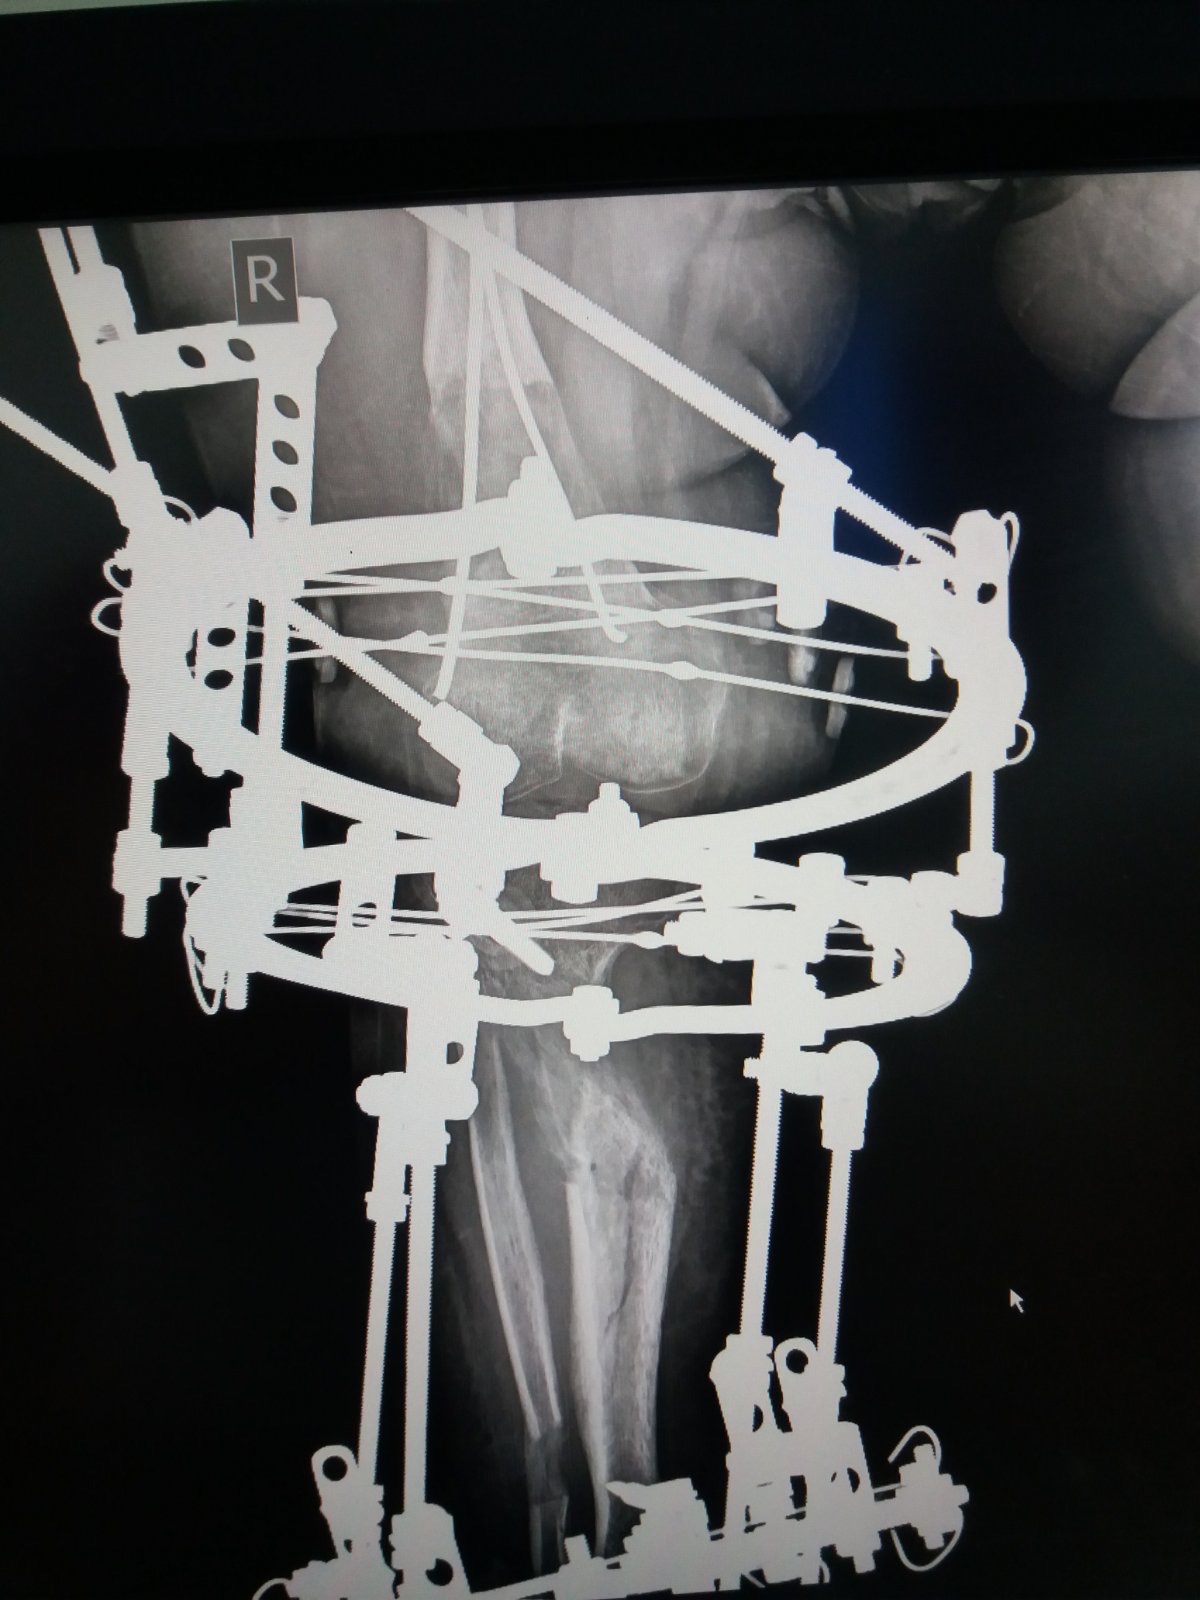

You can see the results of the treatment on the video. This was on January 2nd last year. When we looked and saw that the lengthened bones had grown properly and then we took off Ilizarov’s apparatus. It was necessary to wear the plaster for a certain time, so that the patient could use her leg without any fear. Also, to start walking in the period from when we removed the device until this examination. In the future, she should do exercise for the knees, ankle, and to strengthen her muscles.

And now you were wearing this Ilizarov apparatus, was it hard?

Elma: “Well, it is, it’s quite hard, a little annoying.”

Are you going to keep wearing Ilizarov now or are you done with him?

Elma: “I have another leg extension operation and then I will wear it the most.”

The right doctor was found in the Atlas Hospital in Belgrade. Dad Nusret showed us a picture where you can see how big the problem was with Elma’s legs. They were in the shape of the letter O, and in the case of the left, the deformity was greater because the bone in the axis was completely inverted. After the operation and wearing the apparatus they are corrected now and parent’s happiness is endless. Every inch was important to them.